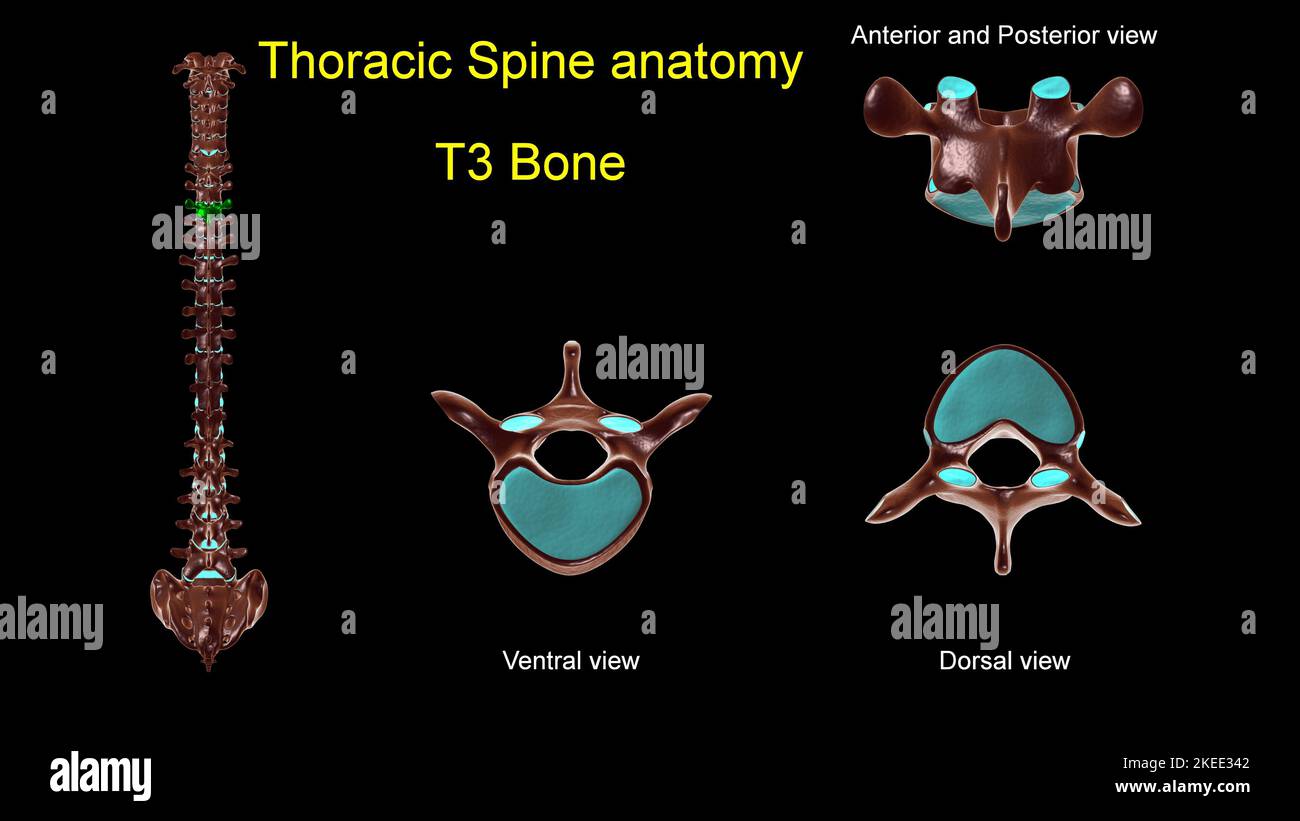

RF2KEE32B–Colonna toracica T 1 anatomia ossea per concetto medico 3D Illustrazione con vista anteriore e posteriore

RF2KEE329–Colonna toracica T 11 anatomia ossea per concetto medico 3D Illustrazione con vista anteriore e posteriore

RF2KEE342–Colonna toracica T 3 anatomia ossea per concetto medico 3D Illustrazione con vista anteriore e posteriore

RF2KEE326–Colonna toracica T 4 anatomia ossea per concetto medico 3D Illustrazione con vista anteriore e posteriore

RF2KEE34K–Colonna toracica T 7 anatomia ossea per concetto medico 3D Illustrazione con vista anteriore e posteriore

RF2KEE333–Colonna toracica T 6 anatomia ossea per concetto medico 3D Illustrazione con vista anteriore e posteriore